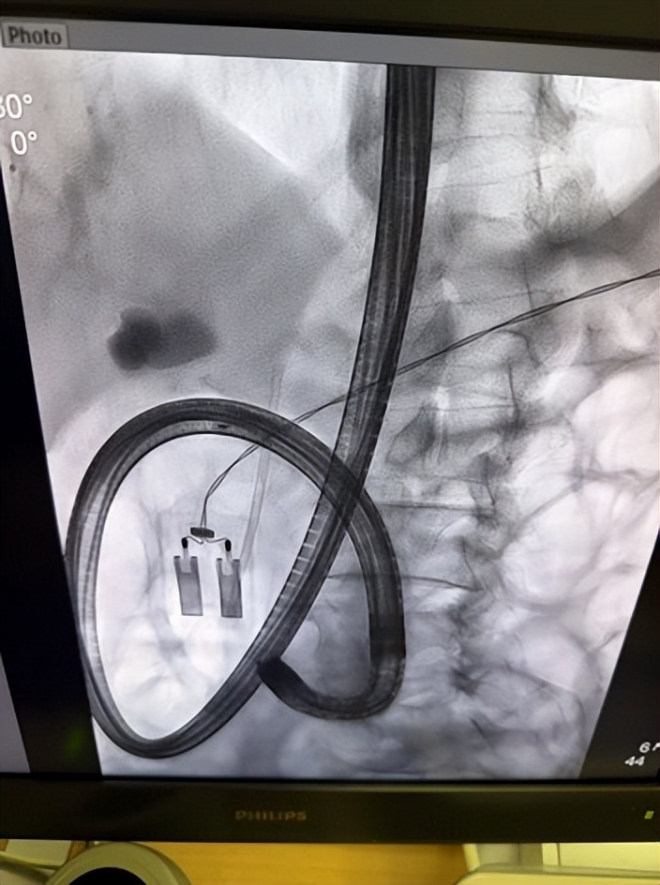

成功插管造影后,X线清晰显示胆总管下段有一枚直径约1.2cm的结石影,造成胆道梗阻和扩张。考虑到患者特殊的术后解剖结构、所用胃镜的工作长度限制以及一次性彻底取石可能带来的高风险,团队以患者安全为首要原则,制定了分步治疗的策略:本次手术的核心目标是迅速解除梗阻、引流淤积的胆汁、控制感染。于是,手术团队沿导丝精准置入一枚7Fr“圣诞树”塑料支架。支架的放置犹如在堵塞的胆道中架起了一座“高架桥”,胆汁得以顺利流入肠道,患者的梗阻症状随即得到显著缓解。手术达到预期目标,患者安返病房。